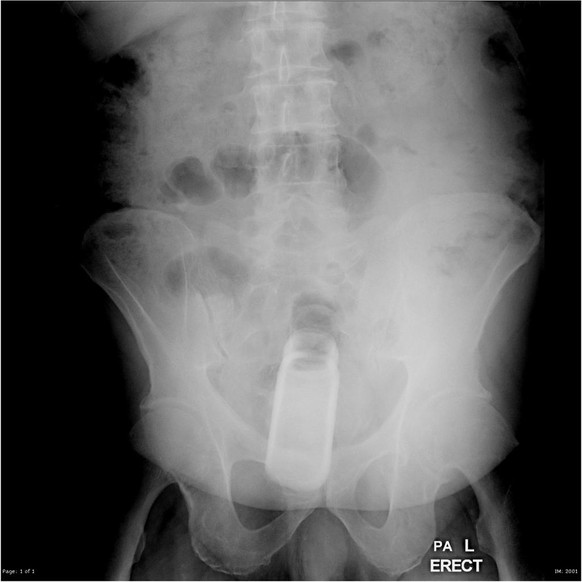

Ein Ei

Zum guter Letzt ein besonders kurioser Fall. Denn hier wurde der Gegenstand nicht etwa aus Gründen der sexuellen Stimulation, sondern der Selbstmedikation eingeführt.

Der Fall soll aus dem Archiv eines iranischen Arztes stammen, der eine Patientin aus einer ländlichen Gegend behandelte, in der das Einführen eines Eies zur Schmerzlinderung vollzogen wurde. Hierbei ging es wohl um Schmerzen, die durch einen Knochenbruch verursacht wurden, wie auf dem Bild zu sehen.